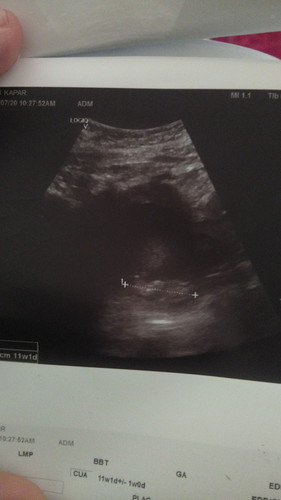

fabroid ketika hamil

doc sahkan saya ada fabroid ketika hamil, doc kata kemungkinan baby makin besar dan fabroid akan hilang dengan sendiri, ataupun fabroid makin besar, saya terpaksa menjalani pembedahan dan baby mungkin lahir premature. soalan saya, anda ada pengalaman seperti ini? saya down seketika. tapi saya usaha jaga makan disamping baca doa (bg yg islam)